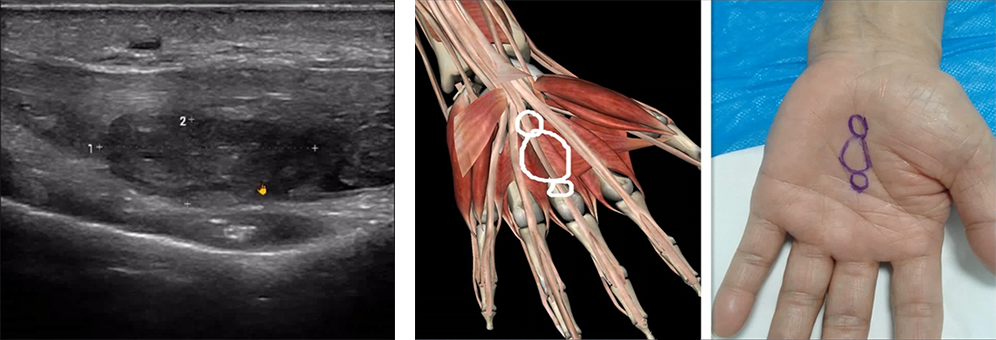

The patient experienced a noticeable snapping sensation in the wrist during active flexion of the interphalangeal joints.

Ultrasound detected a solid mass causing carpal tunnel syndrome.

This example showcases the role of POCUS in identifying and managing conditions like carpal tunnel syndrome, particularly in cases where traditional diagnostic methods might fall short.